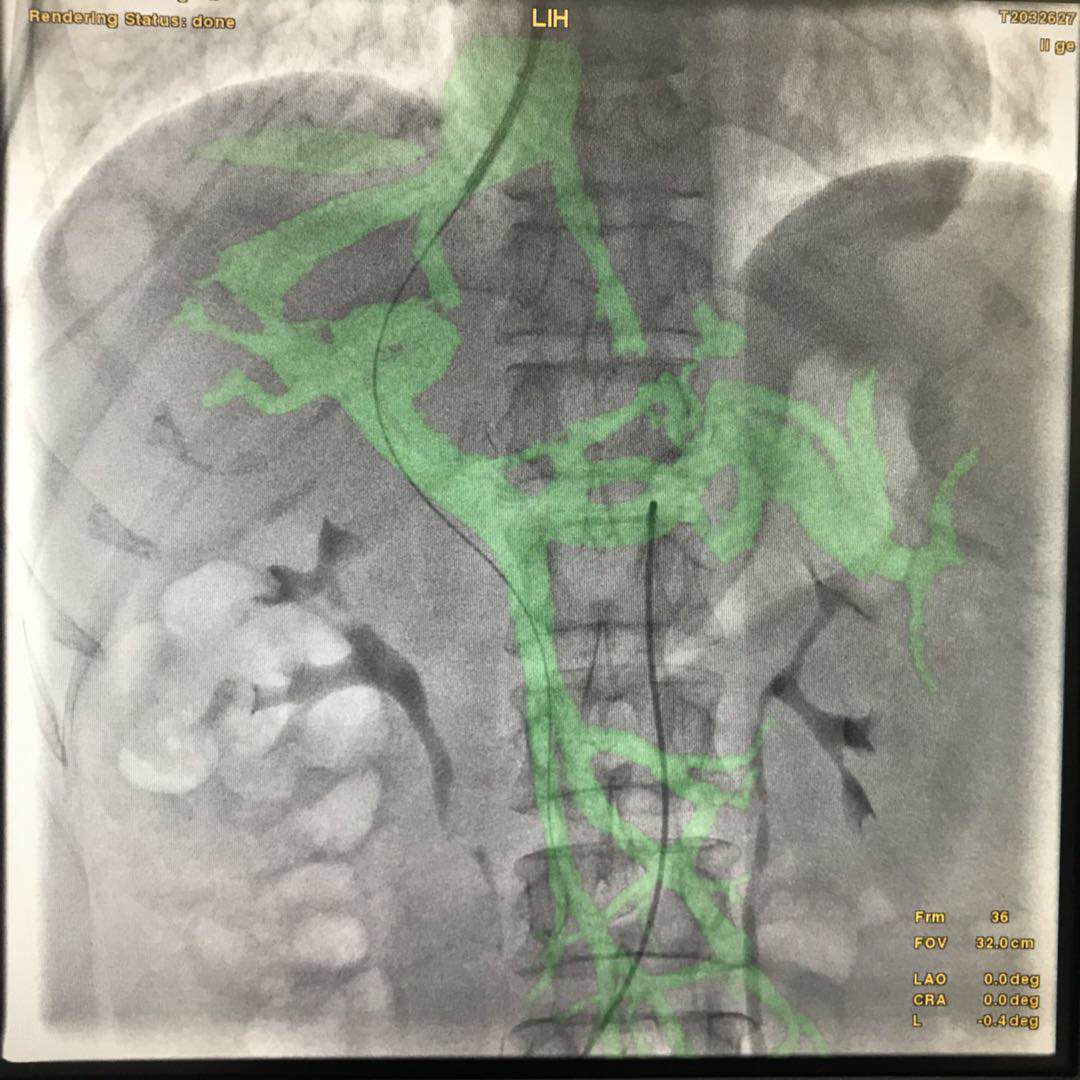

要想安全、准确地完成TIPSS手术,对术者的技术要求非常高。手术前,术者要通过术前的影像学资料:上腹部增强CT或MRI非常明确肝静脉和门静脉的解剖位置关系:即穿刺针进入到肝静脉后,术者要在头脑中把影像学中两者的前后左右位置关系转换成进针角度,把两者的距离远近转换成穿刺深度。如果对角度把握不准确,则很难穿中门静脉;如果对距离远近估计有误,穿刺深度不够时很难穿中门静脉,穿刺过深时,一旦穿刺到肝外门静脉,则容易出现术中腹腔大出血,严重威胁患 的呢?操作步骤非常简单:1、获得患者术前上腹部CTA/MRA图像,以此为基础,将患者的椎体、肝静脉和门静脉生长出来;;2、在透视下,用骨性标志和术中患者的实际位置进行配准对位,这样生长出来的肝静脉和门静脉的模型与患者实际的血管解剖部位自然也就配准了。不仅如此,在导丝进入肝静脉后我们还可以将肝静脉的模型和患者再次进行精准对位3、在透视下,我们可以直接按照智能路图来对着门静脉的方向进行穿刺在此过程中,只要患者相对于导管床的位置不变,无论机架角度和导管床的位置如何变换,智能路图的影像与机架和导管床都是联动的,无需重新对位置,不用担心模型与实际血管错位,如此大大方便了医生从各个角度观察门静脉的走形和位置,及时调整穿刺针的角度和深度。 本周在河南某医院进行了影像融合下引导TIPSS手术,大大提高了手术精度,最大程度地降低了手术风险,减少了操作时间,提高了术者信心。手术图像详见下图: